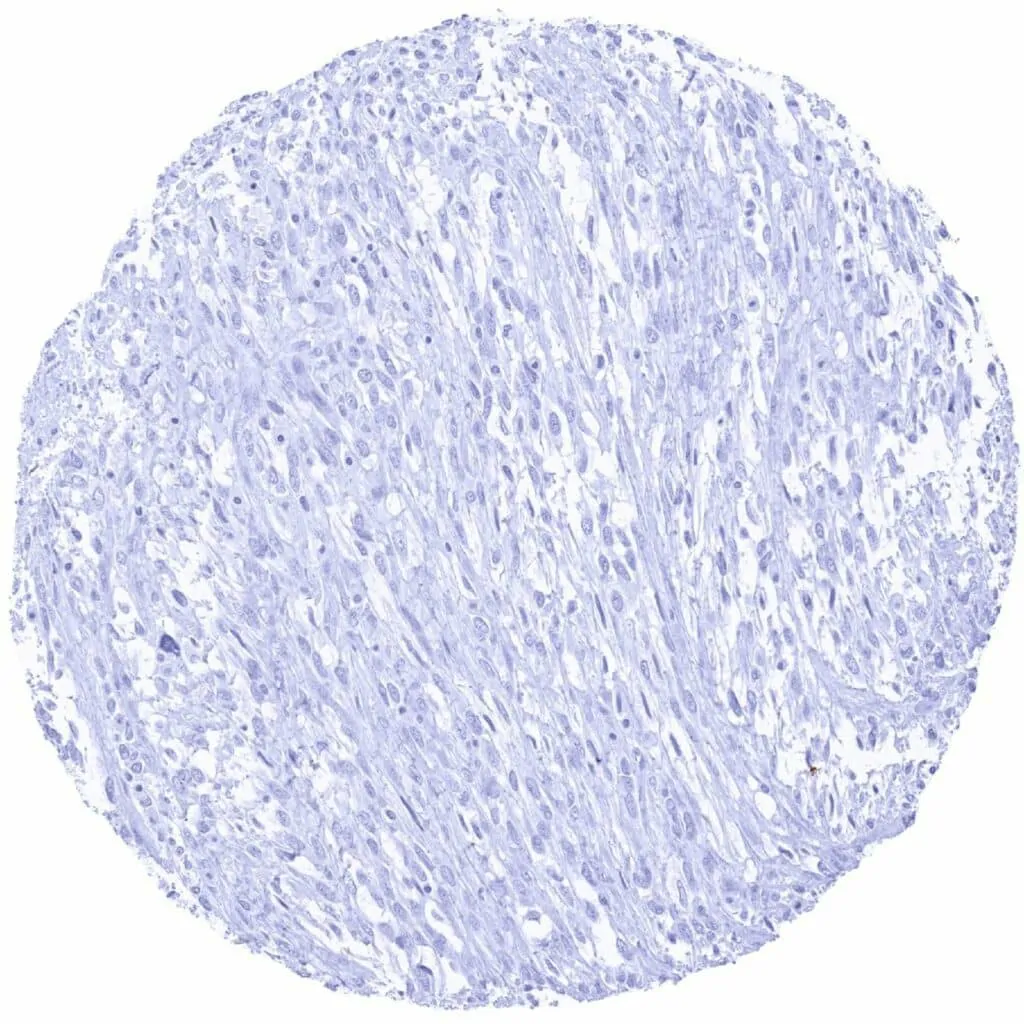

Soft tissue – CD38 negative leiomyosarcoma